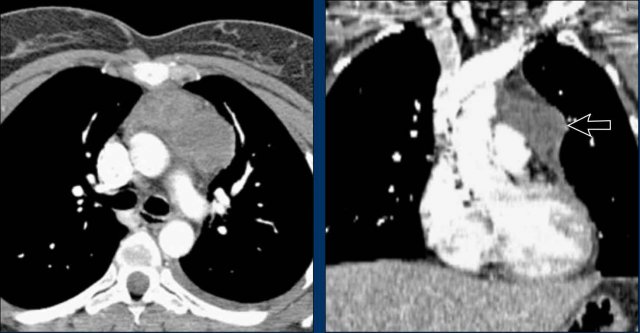

Case Example 1: Pericardial Effusion Mimicking Cardiomegaly

• On the chest radiograph, the patient appears to have a dilated heart.

• However, CT imaging clearly demonstrates that the apparent enlargement is due to significant pericardial fluid accumulation, not true myocardial chamber enlargement.

Case Example 2 - CT imaging

• CT imaging revealed a large posterior pericardial effusion compressing the left ventricle (blue arrow: effusion; red arrow: compressed, contrast-filled left ventricle).

• Surgical exploration confirmed a large posterior pericardial hematoma.

Note

: Minimal anterior fluid on ultrasound may underestimate the true volume if the effusion is loculated posteriorly, highlighting the value of CT in postoperative cases.